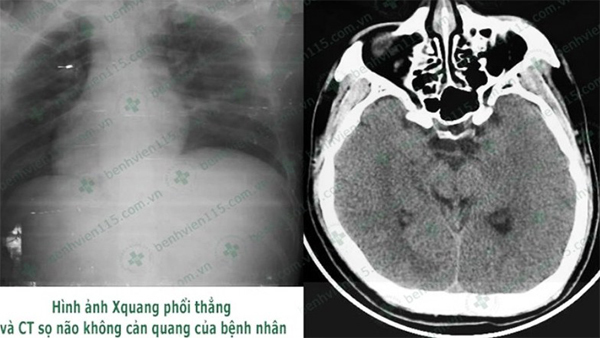

Người đàn ông thoát chết, bất ngờ với lý do đi ngủ quên đóng cửa lúc nửa đêm

Nửa đêm, hàng xóm ông C. tỉnh giấc, phát hiện nhà ông vẫn sáng đèn, cửa không đóng nên vào kiểm tra, phát hiện nam bệnh nhân bất tỉnh nên tri hô mọi người đưa ông đi cấp cứu.